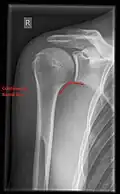

Imaging

Imaging of the shoulder includes ultrasound, X-ray and MRI, and is guided by the suspected diagnosis and presenting symptoms.

Conventional x-rays and ultrasonography are the primary tools used to confirm a diagnosis of injuries sustained to the rotator cuff. For extended clinical questions, imaging through Magnetic Resonance with or without intraarticular contrast agent is indicated.

Hodler et al. recommend starting scanning with conventional x-rays taken from at least two planes, since this method gives a wide first impression and even has the chance of exposing any frequent shoulder pathologies, i.e., decompensated rotator cuff tears, tendinitis calcarea, dislocations, fractures, usures, and/or osteophytes. Furthermore, x-rays are required for the planning of an optimal CT or MR image.[25]

X-ray

Projectional radiography views of the shoulder include:

AP-projection 40° posterior oblique after Grashey

The body has to be rotated about 30 to 45 degrees towards the shoulder to be imaged, and the standing or sitting patient lets the arm hang. This method reveals the joint gap and the vertical alignment towards the socket.[26]

Transaxillary projection

The arm should be abducted 80 to 100 degrees. This method reveals:[26]

• The horizontal alignment of the humerus head in respect to the socket and the lateral clavicle in respect to the acromion

• Lesions of the anterior and posterior socket border, or of the tuberculum minus

• The eventual non-closure of the acromial apophysis

• The coraco-humeral interval

Y-projection

The lateral contour of the shoulder should be positioned in front of the film in a way that the longitudinal axis of the scapula continues parallel to the path of the rays. This method reveals:[26]

• The horizontal centralization of the humerus head and socket

• The osseous margins of the coraco-acromial arch and hence the supraspinatus outlet canal

• The shape of the acromion

This projection has a low tolerance for errors and, accordingly, needs proper execution.[26] The Y-projection can be traced back to Wijnblath’s 1933 published cavitas-en-face projection.[27]